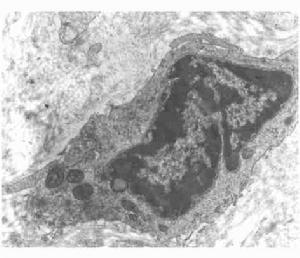

放射複合傷時,由於小腸黏膜上皮,尤其是隱窩的幹細胞庫對射線十分敏感,故很容易受到破壞。大劑量照射後,小腸隱窩核分裂相消失,出現核壞死。未壞死的細胞核邊緣不清晰,核膜缺損,核扭曲。染色質間顆粒減少消失。絨毛各段上皮細胞壞死脫落。傷後2天,絨毛枯瘦,上皮細胞變矮、增寬。隱窩進行性破壞、崩解。隱窩和絨毛下部主要由畸形細胞構成。畸形細胞的異常核分裂,有的發生增殖死亡。腸上皮壞死細胞清除遲緩。小腸3H-TdR摻入率降低,小腸腸壁血循環障礙,腸壁各層淤血水腫明顯。有時由於腸蠕動增強等原因,可以並發腸套疊。腸套疊多發生於迴腸,一旦發生,將造成急性梗阻。在臨床上常表現出胃腸道功能紊亂。食慾減退、厭食、拒食、噁心、嘔吐、腹瀉等消化道症狀出現早、且嚴重。腹瀉常為水樣便或血水樣便。

放射複合傷後,骨髓造血組織損傷明顯加重,造血細胞減少,造血組織幾乎全為脂肪細胞所代替。骨髓發生空虛的時間較相應劑量的單純放射病提前;放射複合傷時,粒系造血抑制主要是中幼粒細胞以前的具有分裂能力的粒系幼稚細胞受到抑制,並且較單純照射更為嚴重。放射複合傷貧血是大細胞低色素性的。此時骨髓幼稚紅細胞受到明顯抑制,紅系造血祖細胞受抑制出現早、恢復遲。放射複合傷貧血的原因,除紅系統造血抑制外,體內內環境可加速紅細胞破壞,使紅細胞的半生存期縮短。

放射複合傷時,除造血實質細胞受累外,造血微環境也受到明顯影響。傷後骨髓細胞貼壁率降低和骨髓基質祖細胞減少均較單傷明顯。放射複合傷傷後2天,造血組織及外周血中的核酸含量,無論是DNA或RNA,都有隨照射劑增加而顯著降低的趨勢。DNA較RNA減少更為明顯。